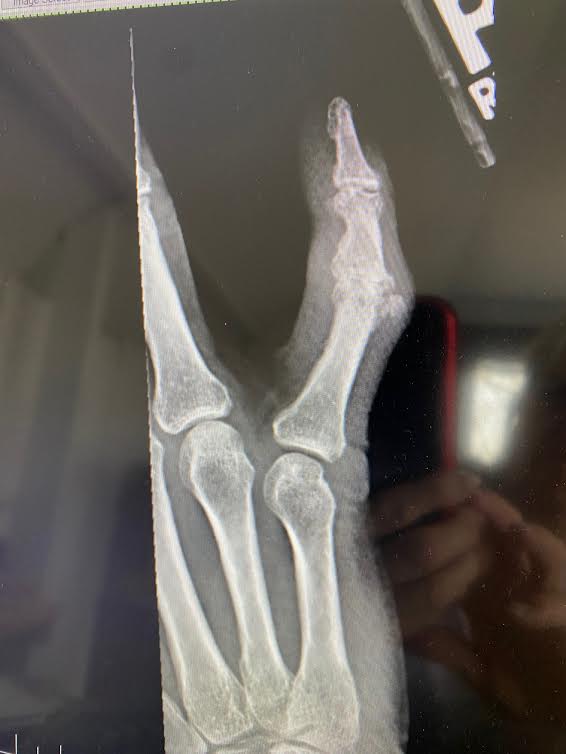

I broke the knuckle straight across and knocked a chip out of it.

Arthritis has taken over the first knuckle and will take over the tiny knuckle at the tip.

So there you have it: pain, lingering, hovering, whispering constantly—letting me know I have a little finger, which now hangs outside of the normal part of my hand, catching on things, finding little ways to let me know—